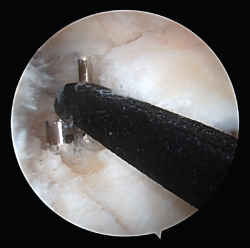

Figure 6. View from the anterolateral portal of the intraarticular positioning of the guide and the intraarticular exit of the tunnels at the footprint of the posterior root of the internal meniscus of a right knee.

One of the patients in the standard guide group required modification of the perforation secondary to intraarticular exit of the Kirschner wire in a position different from that planned, due to positioning difficulties caused by the existence of a narrow intercondylar groove and prominent spines. The 3D printed guides adapted on both supports to the bone surface of the tibia and were precise in conducting the guide needles towards the planned position (Figures 6 and 7). There were no problems derived from friction between the metal of the needles and the bore of the customized guide, and handling was ergonomically satisfactory for the surgeon.